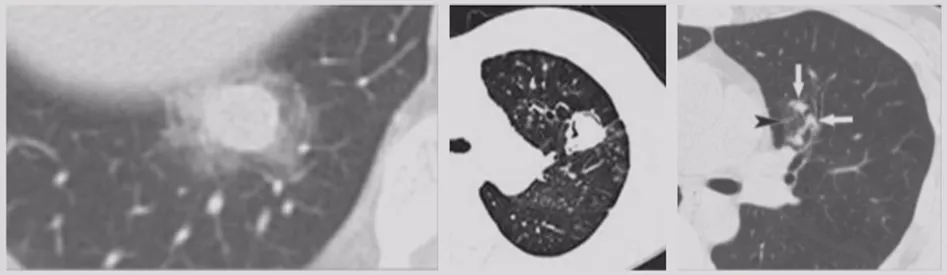

如上图所示,一般来说这么小的病灶我们可能忽略,但这个病人做了手术,不仅是恶性肿瘤,而且是微浸润腺癌。实际上我们在临床上要把这么多结节甄别出来,是十分具有挑战性的。病人一旦患有肺结节,也面临着很多问题,比如焦虑、心理压力等。所以我们既不能过度诊断,但也不能延误诊断。

内部特征:燕麦圈征(开放支气管征)

还有非常容易被大家忽略的一个特点(如上图所示),文献上把这个病灶称为燕麦圈征,这不是个好征象。由开放气道周围的肿瘤细胞或非肿瘤细胞增生所致,多见于肺腺癌和肺朗格汉斯细胞组织细胞增多症。尤其是女性病人出现这种征象的概率比较高,出现之后一定要手术。

内部特征:空洞

空洞可在坏死性恶性结节如鳞状细胞癌中看到,也可见于良性结节,如脓肿、感染性肉芽肿、血管炎、淋巴细胞性间质性肺炎、早期的朗格汉斯细胞组织细胞增生症、肺梗死。

这个征象大家也要特别注意,当周围空腔壁增厚、空腔壁上出现结节时须高度关注,不要认为这样的都是肺大泡而把它漏诊。